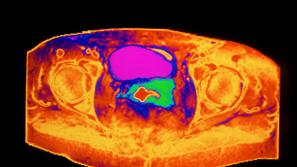

To je rak, ki je velika izjema. Bo Slovenija prva?

Rak materničnega vratu je med raki izjema, saj o njem vemo dovolj, da lahko preprečimo skoraj vsak nov primer. Sloveni…